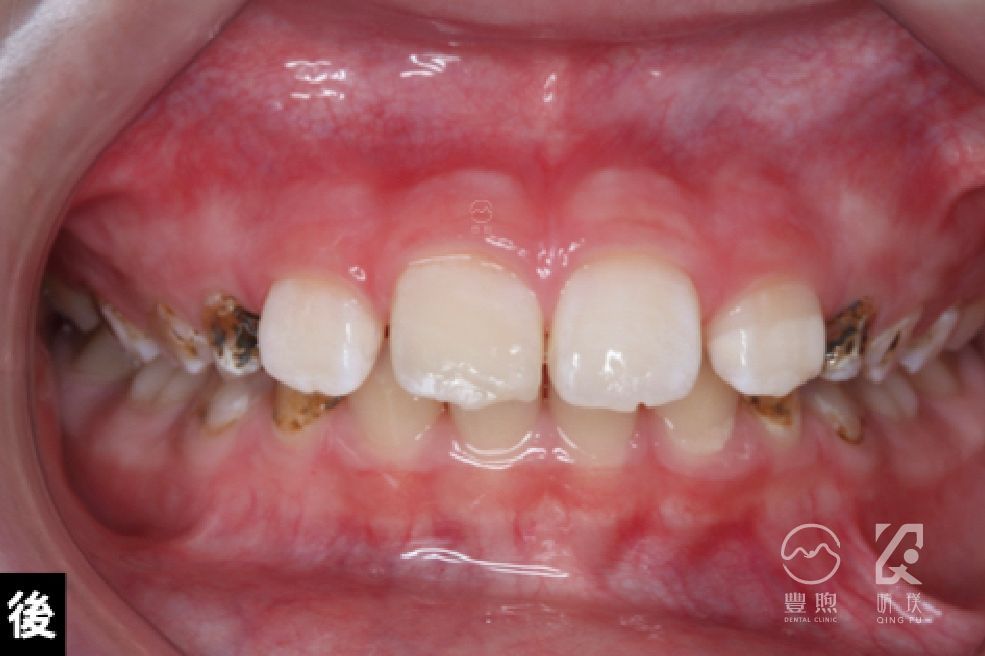

門牙斷裂黏著修復

經臨床及X光片檢查下,確認牙齒傷害程度,然後在充分隔濕環境下,將牙齒斷裂部分黏著回去。

這位孩童剛好屬於第一類,所以可以做簡單的處置就恢復牙齒外觀,但強度肯定沒有原先來的好,考量到病人年紀,先保守處理,等牙齒及牙弓完善發育後再看看是否需要做進一步的治療。